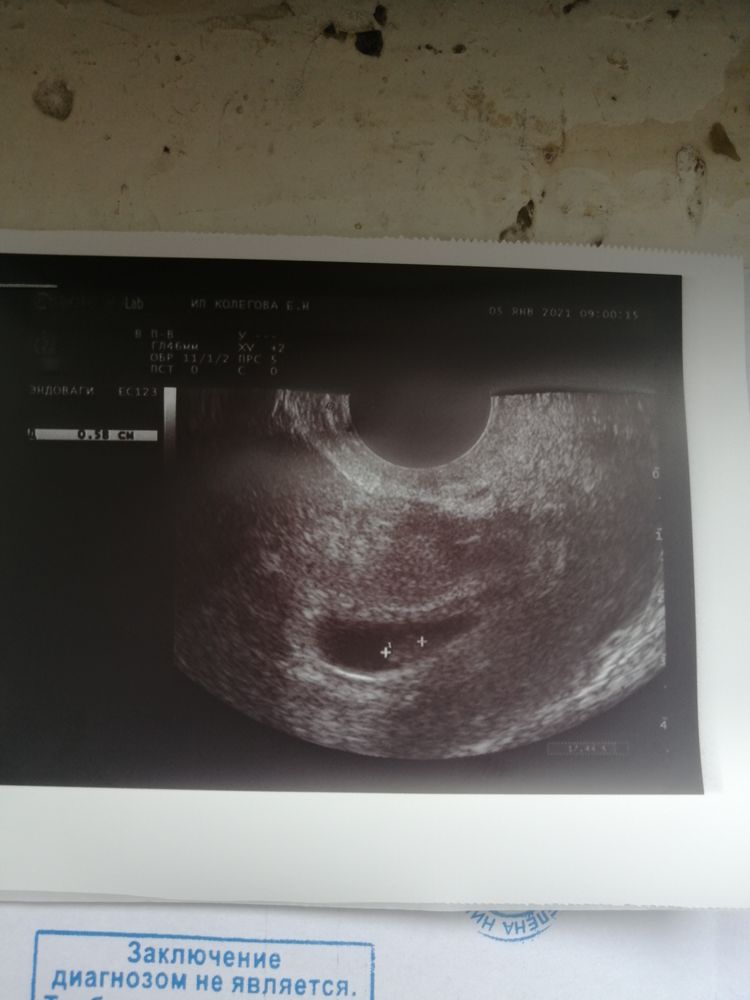

Посмотрите кто у нас будет? Оба узи, разница в 4 недели трансвагинально

30.03.2021